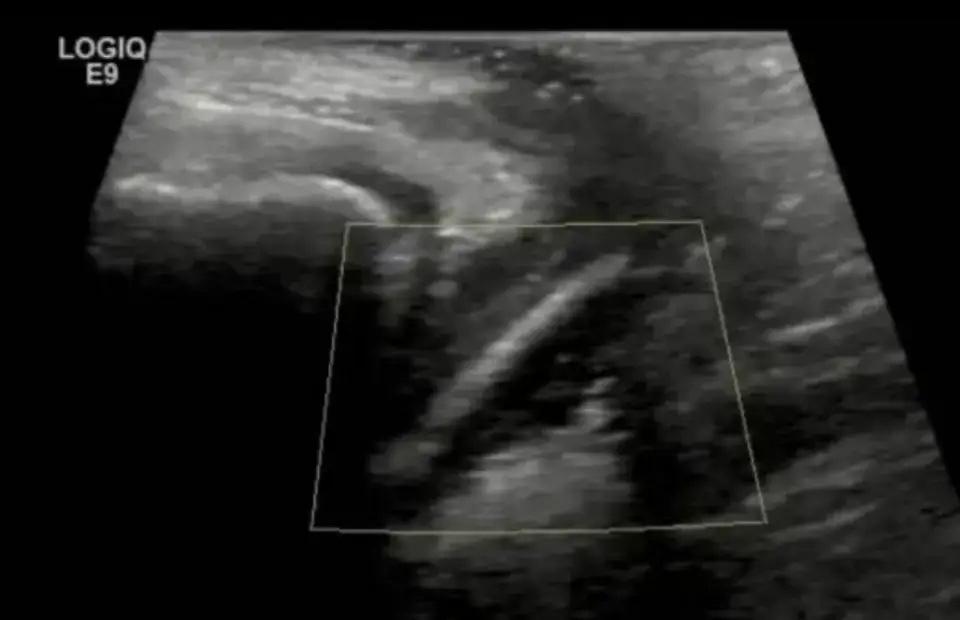

检查结果出来阴道里真卡着东西,一支完整的试用装精华液塞在里面。孩子这才小声承认,一个月前好奇,偷偷放进去的。妈妈当场就懵了,哪能想到是这个原因。

医生赶紧安排内镜手术把东西取了出来,好在处理及时没伤到孩子,当天就能出院回家。一支小小的精华液,差点惹出大麻烦。